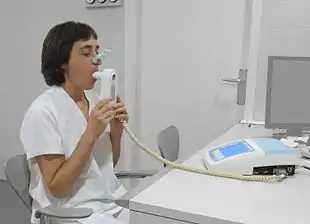

| Diagnostic method | Spirometry[4] |

The most common cause of COPD is tobacco smoking.[16] Other risk factors include indoor and outdoor air pollution including dust, exposure to occupational irritants such as dust from grains, cadmium dust or fumes, and genetics, such as alpha-1 antitrypsin deficiency.[12][17] In developing countries, common sources of indoor air pollution are the use of coal and biomass such as wood and dry dung as fuel for cooking and heating.[18][12] The diagnosis is based on poor airflow as measured by spirometry.[4]

Diagnosis

The diagnosis of COPD should be considered in anyone over the age of 35 to 40 who has shortness of breath, a chronic cough, sputum production, or frequent winter colds and a history of exposure to risk factors for the disease. Spirometry is then used to confirm the diagnosis.[4][101]

Spirometry

Spirometry measures the amount of airflow obstruction present and is generally carried out after the use of a bronchodilator, a medication to open up the airways.[102] Two main components are measured to make the diagnosis, the forced expiratory volume in one second (FEV1), which is the greatest volume of air that can be breathed out in the first second of a breath and the forced vital capacity (FVC), which is the greatest volume of air that can be breathed out in a single large breath.[103] Normally, 75–80% of the FVC comes out in the first second[103] and a FEV1/FVC ratio less than 70% in someone with symptoms of COPD defines a person as having the disease.[102] Based on these measurements, spirometry would lead to over-diagnosis of COPD in the elderly.[102] The National Institute for Health and Care Excellence criteria additionally require a FEV1 less than 80% of predicted.[104] People with COPD also exhibit a decrease in diffusing capacity of the lung for carbon monoxide due to decreased surface area in the alveoli, as well as damage to the capillary bed.[105] Testing the peak expiratory flow (the maximum speed of expiration), commonly used in asthma diagnosis, is not sufficient for the diagnosis of COPD.[104]

Screening using spirometry in those without symptoms has uncertain effect and is generally not recommended; however, it is recommended for those without symptoms but with a known risk factor.[42]